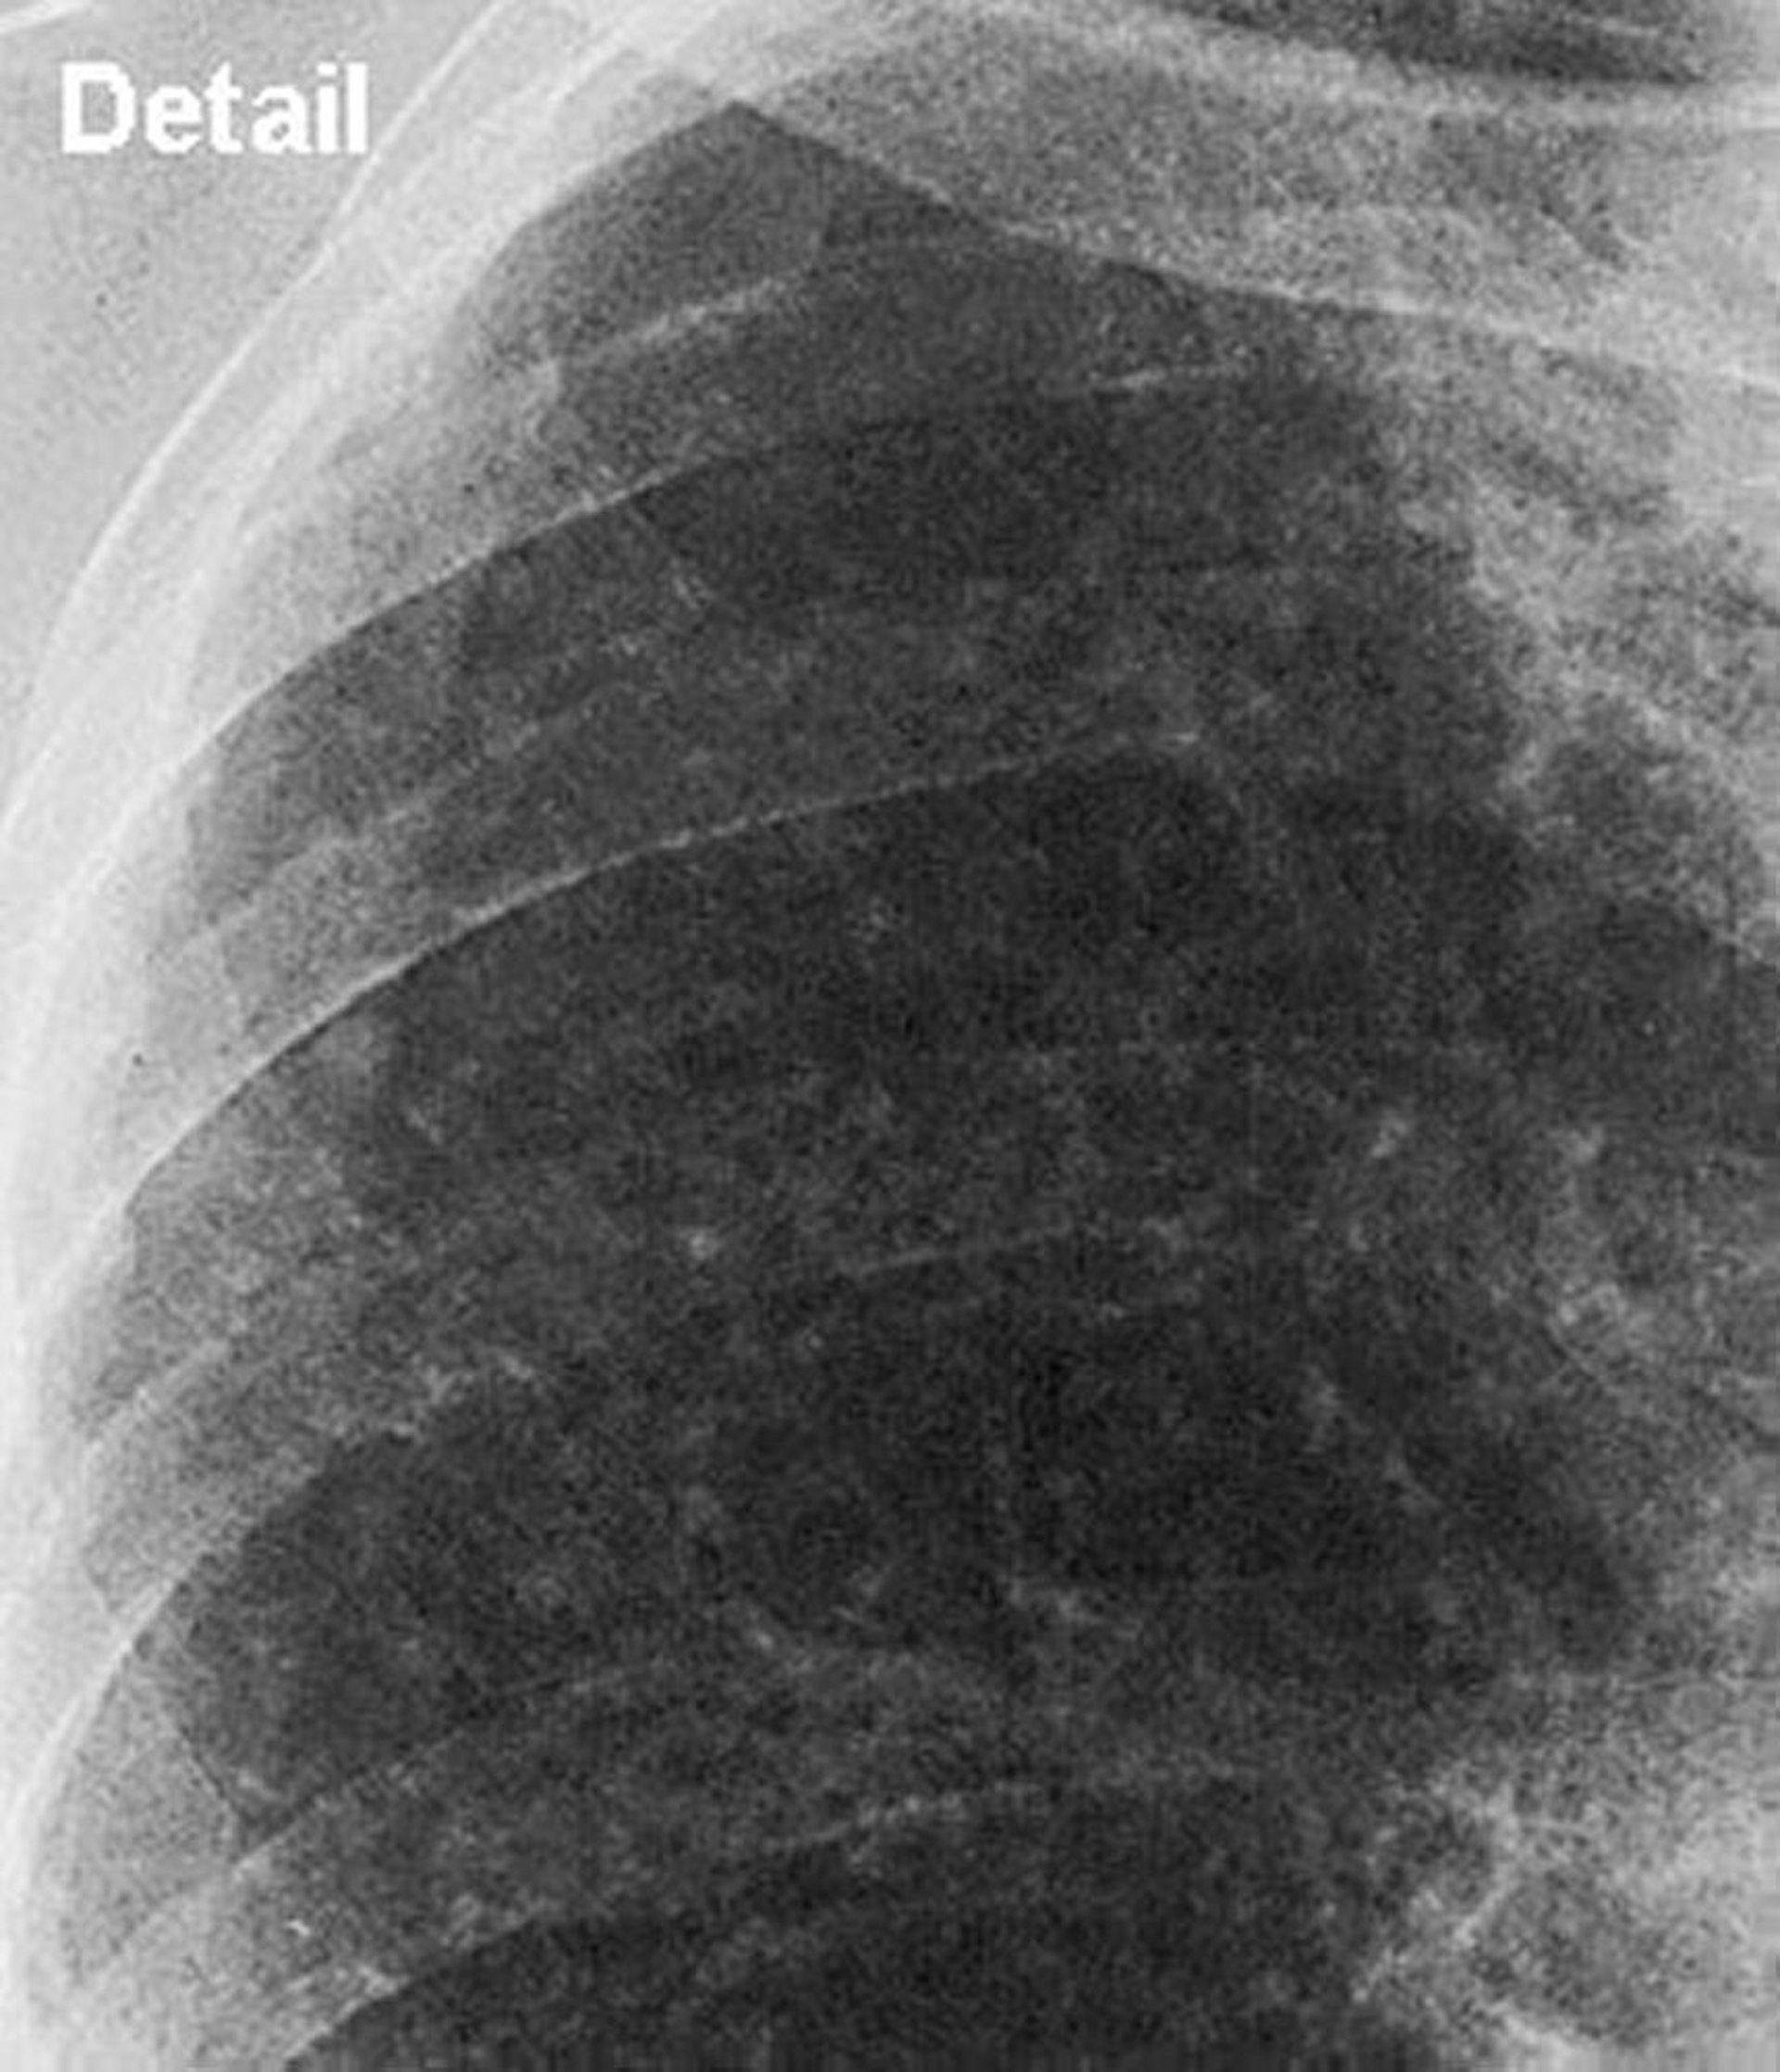

Silicosis: forma simple (campo pulmonar superior)

Vista de aproximación del campo pulmonar superior en la silicosis simple.